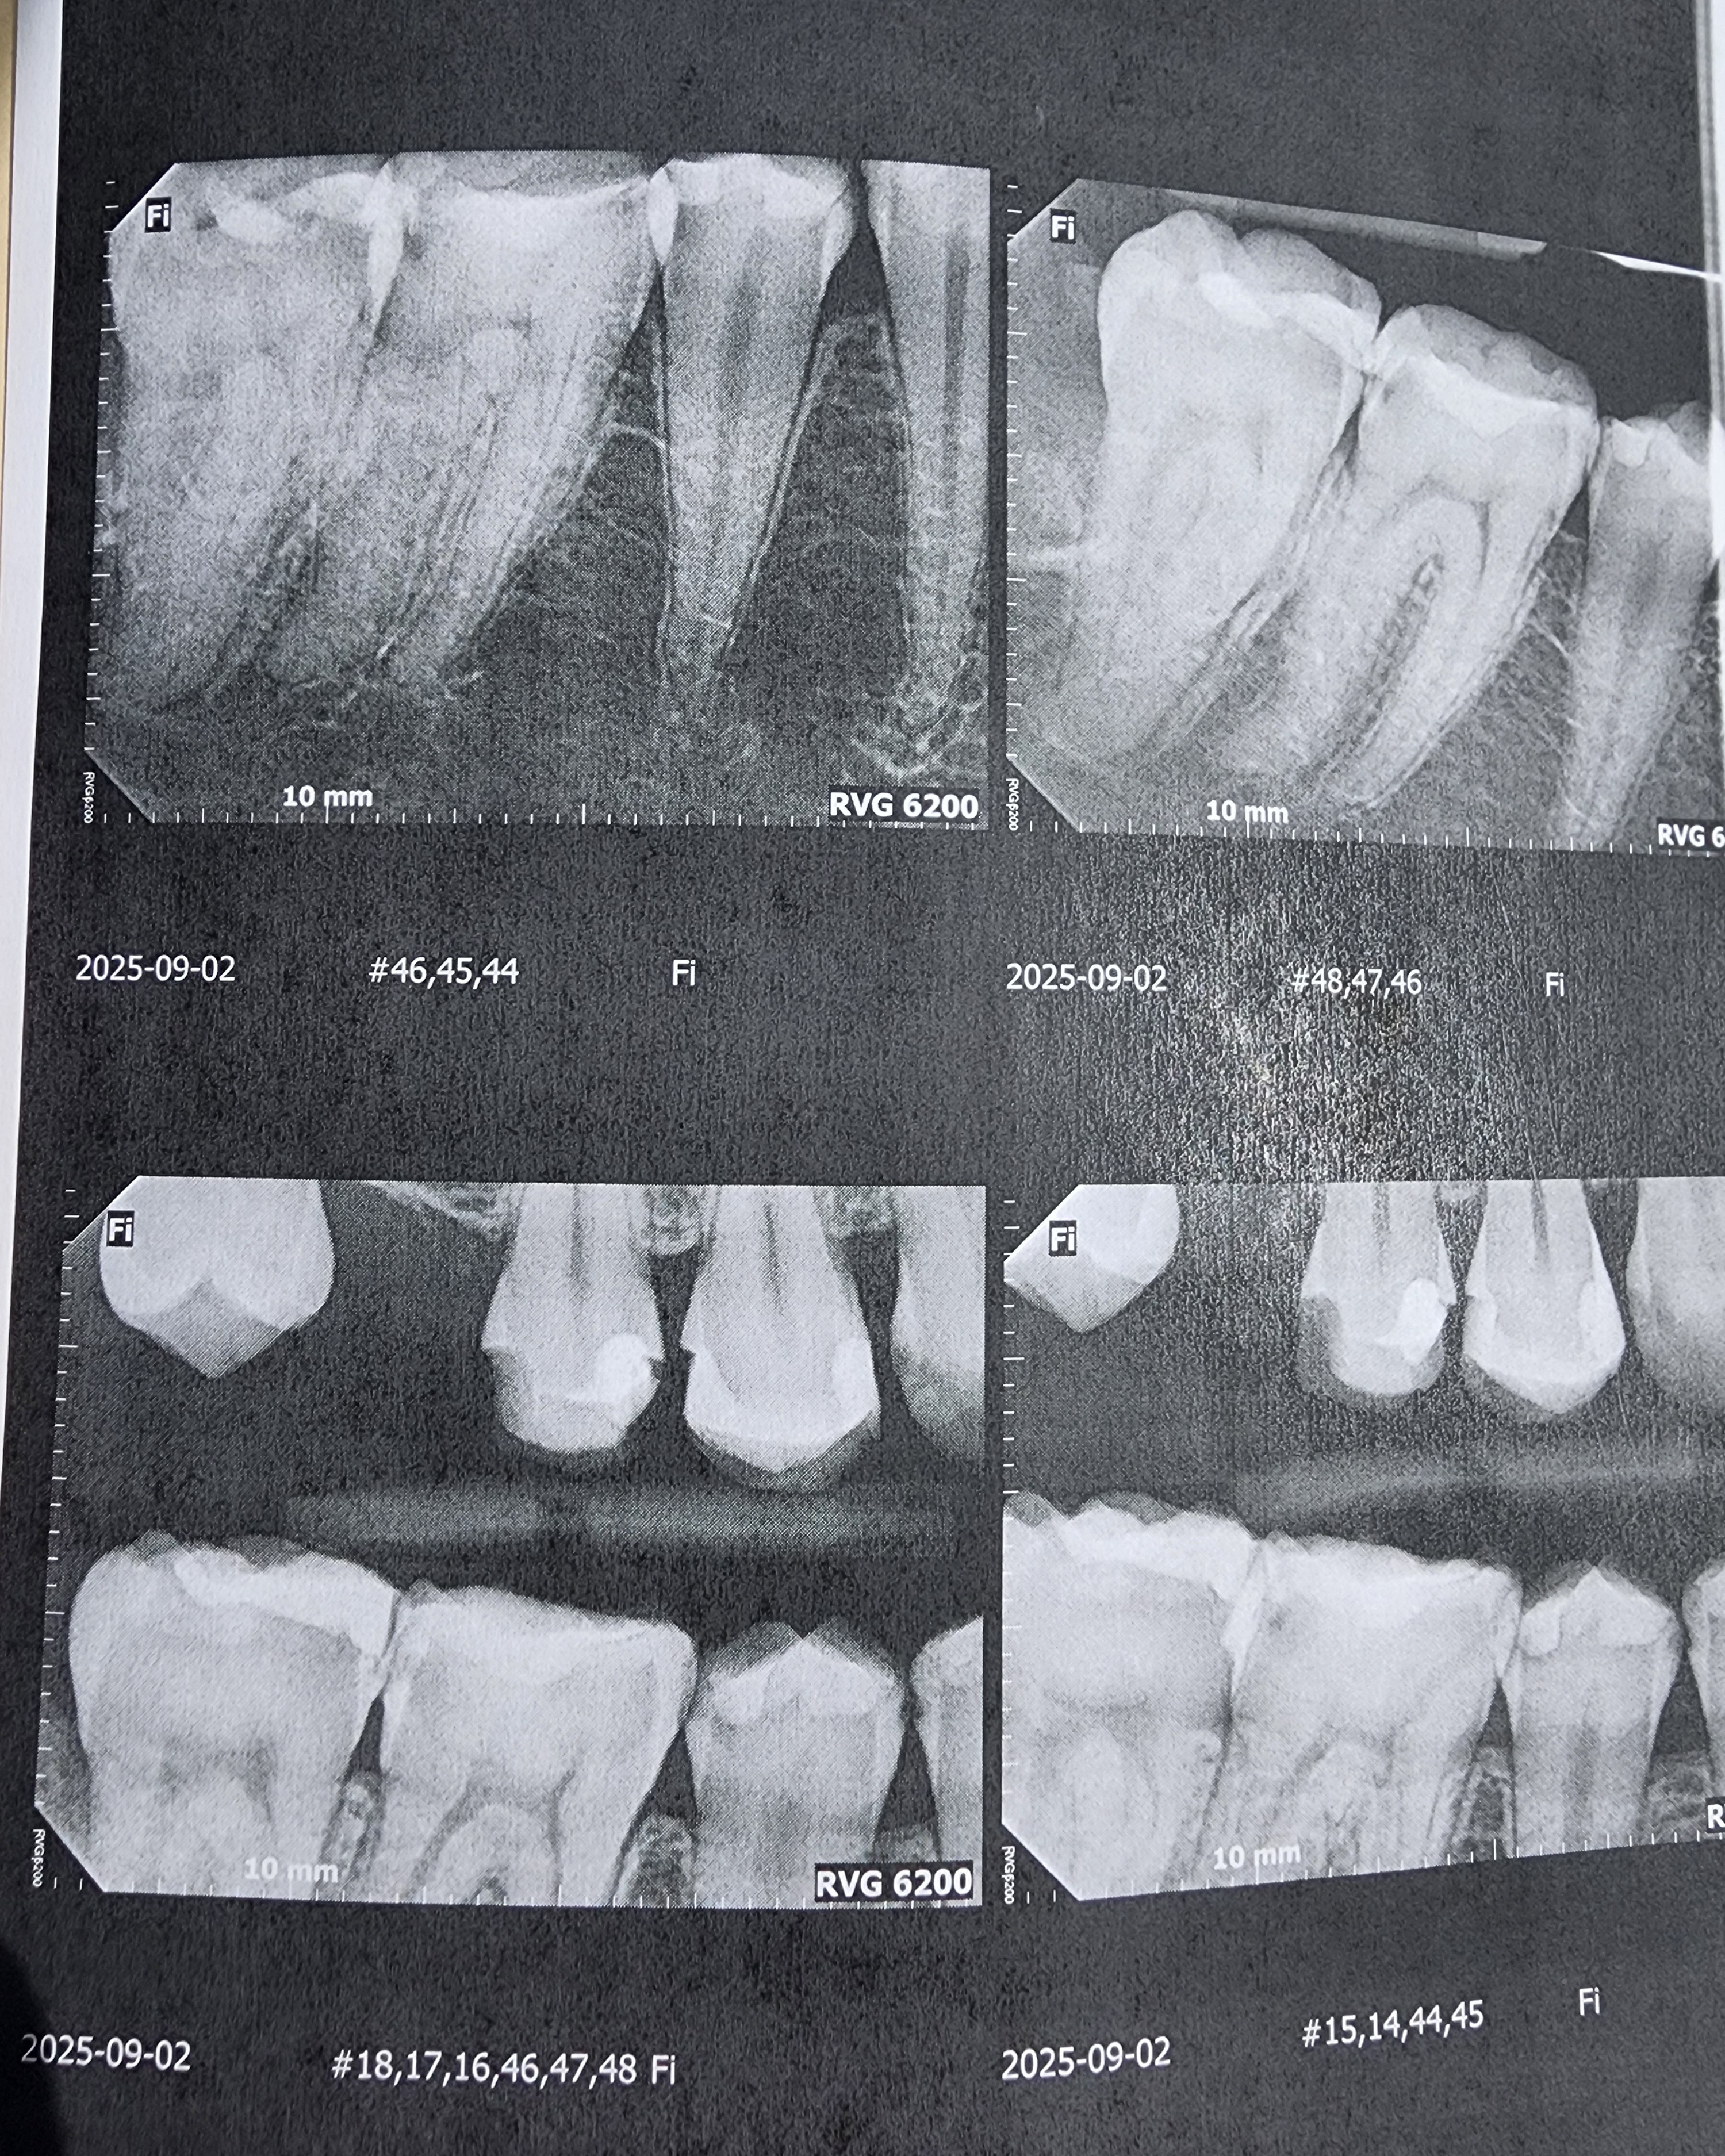

Hello. My name is Ash and those x-rays are of my not so good teeth. I knew that they weren't that good but they were worse than I could ever have imagined.

Due to an old dentist seemingly giving me bad fillings before leaving the practice, it seems I need 4 Crowns, 1 or 2 Root Canals, and a whole ton of fillings. I was prepared for a couple thousand but it seems they want about 12,400 in total. And this includes a dental plan card they let me sign up for to half the entire bill. They want me to pay before each appointment and at this point I dont know what I can do.